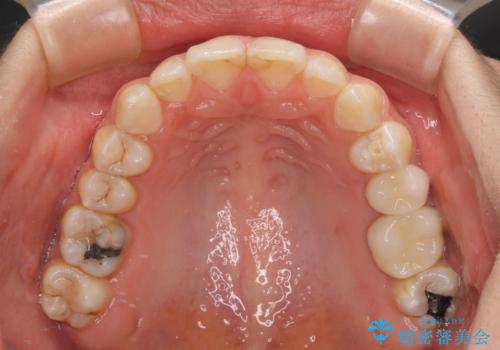

咬み合わせと目立っていた銀歯が改善され、患者様には大変満足していただきました。